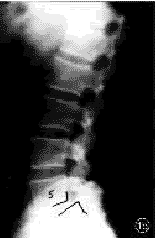

图1 患者男,50岁。术前X线片示L4,5Ⅰ度滑脱移位

1a 术前X线正位片 1b 术前X线侧位片